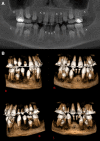

There are more than 900 genetic syndromes associated with oral manifestations. These syndromes can have serious health implications, and left undiagnosed, can hamper treatment and prognosis later in life. About 6.67% of the population will develop a rare disease during their lifetime, some of which are difficult to diagnose. The establishment of a data and tissue bank of rare diseases with oral manifestations in Quebec will help medical professionals identify the genes involved, will improve knowledge on the rare genetic diseases, and will also lead to improved patient management. It will also allow samples and information sharing with other clinicians and investigators. As an example of a condition requiring additional research, dental ankylosis is a condition in which the tooth's cementum fuses to the surrounding alveolar bone. This can be secondary to traumatic injury but is often idiopathic, and the genes involved in the idiopathic cases, if any, are poorly known. To date, patients with both identified and unidentified genetic etiology for their dental anomalies were recruited through dental and genetics clinics for the study. They underwent sequencing of selected genes or exome sequencing depending on the manifestation. We recruited 37 patients and we identified pathogenic or likely pathogenic variants in WNT10A, EDAR, AMBN, PLOD1, TSPEAR, PRKAR1A, FAM83H, PRKACB, DLX3, DSPP, BMP2, TGDS. Our project led to the establishment of the Quebec Dental Anomalies Registry, which will help researchers, medical and dental practitioners alike understand the genetics of dental anomalies and facilitate research collaborations into improved standards of care for patients with rare dental anomalies and any accompanying genetic diseases.